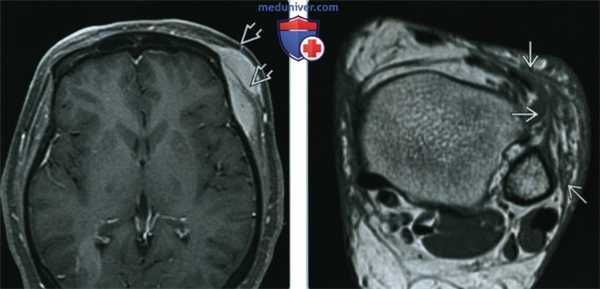

(Слева) МРТ, постконтрастные Т1 ВИ, режим подавления сигнала от жира, аксиальный срез: у пациента с саркоидозом и отеком виска слева определяется контрастируемое мягкотканное образование, проникающее в левую височную мышцу. При биопсии соседнего образования (изображение отсутствует) были обнаружены неказеозные гранулемы. Отмечалось отсутствие изъязвлений нижележащего свода черепа.

(Справа) МРТ, PD-ВИ, аксиальный срез: у женщины с саркоидозом и «образованием» в области голеностопного сустава определяется сетчатое мягкотканное новообразование в области передней поверхности латеральной лодыжки. В биоптате были выявлены неказеозные гранулемы.